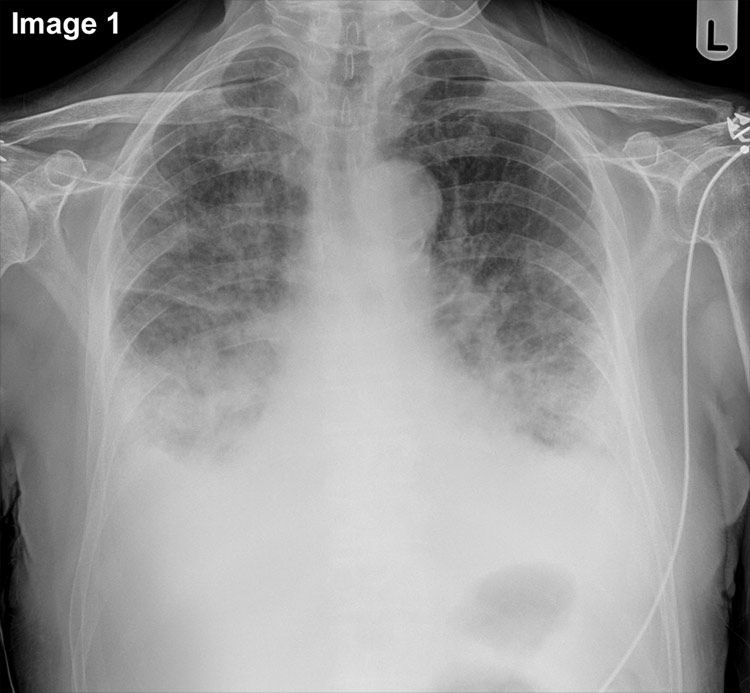

QUIZ: Breathless. Chest pain. (Image 2 = previous). For image 1, which statement is FALSE? A Costophrenic angles are blunt B Upper zone vessels are enlarged C Previous imaging is irrelevant D Image quality is adequate E Image shows heart failure Start Quiz https://t.co/91djR6tPtq